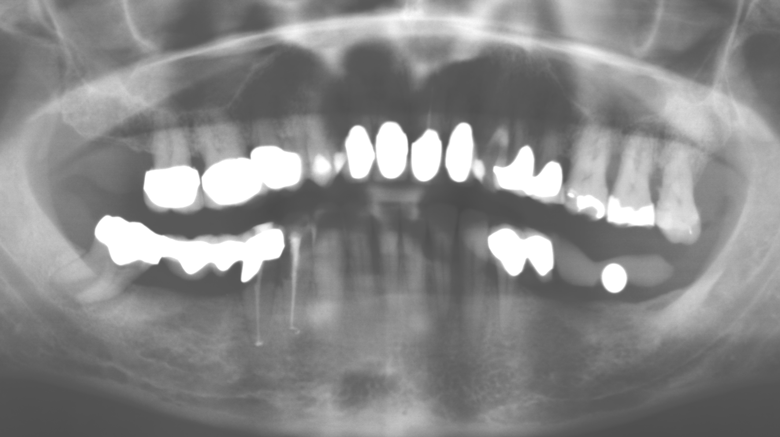

Abb. 1: Panoramaschichtaufnahme des Ausgangsbefundes im Jahr 2004.

Eine 52­-jährige Patientin stellte sich nach Zahnverlust im 3. Quadranten erstmals 2004 vor. Sie hatte den Wunsch nach einer prothetischen Neuversorgung. Im Rahmen der parodontologischen und radiologischen Diagnostik zeigte sich ein ausgeprägter parodontologischer Behandlungsbedarf. Die Zähne 48, 28, 27 zeigten zudem eine infauste Prognose und wurden entfernt (Abb. 1). Nach der erfolgreich abgeschlossenen systematischen PAR­Therapie wurde eine festsitzende implantatprothetische Versorgung mit Insertion von fünf Implantaten in Regio 35, 36, 37 und 46, 47 durchgeführt. Die prothetische Versorgung der natürlichen Zähne erfolgte mit verblendeten Zirkonoxidkeramikkronen, die Implantate wurden mit zweiteiligen individuellen Zirkonoxidabutments und ebenfalls verblendeten Kronen aus einer Zirkonoxidkeramik versorgt (Cercon base colored, Dentsply Sirona Lab). Die definitive Insertion der prothetischen Versorgung erfolgte im Jahr 2005.

Im Rahmen der Zehn­Jahres­Kontrolle zeigten sich keine Hinweise auf einen fortschreitenden parodontalen Attachmentverlust oder einen periimplantären Knochenverlust (Abb. 3).

Abb. 3: Panoramaschichtaufnahme nach einer prothetischen Funktionsperiode von zehn Jahren.